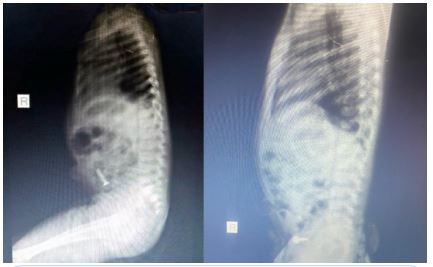

She presented with a plain abdominal radiograph which showed a FB (nail) in the body of the stomach (Figure 1) This was done about 6 hours prior to the presentation at our facility. A repeat radiograph done at the presentation showed the FB (nail) at the region of the terminal ileum (Figure 2). She was commenced on nil per oral, intravenous fluids and monitoring (clinical and radiological). She had two additional plain abdominal radiographs, (Figure 3, 24 hours on admission) and (Figure 4, on day 3). The vital signs remained stable and the abdominal examinations remained equivocal throughout the period of admission. She was discharged following a repeat radiograph which showed no evidence of FB in the GIT.

Figure 2: AP + Lateral view of plain abdominal radiograph. (Done at presentation).